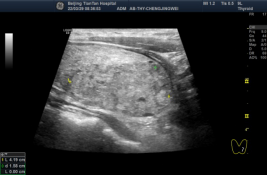

图 术前超声显示甲状腺左叶结节体积过大挤压气管